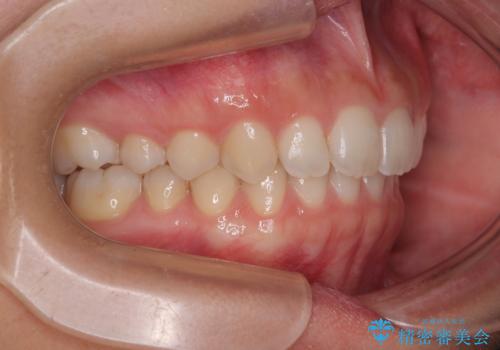

- 上の前歯が前方に飛び出していることを気にして来院された患者様です。

奥歯の咬み合わせをチェックすると、上顎歯列が相対的に前方に位置しているため、補助装置を用いて上顎歯列を確実に後方に移動させ、インビザラインで歯列を整えて行くこととしました。

インビザライン単体でも同様の結果が得られる可能性がありますが、万が一奥歯がうまく後方移動できなかった場合、リカバリーが非常に大変となるため、事前に補助装置を併用して確実に結果が得られるように工夫をしています。